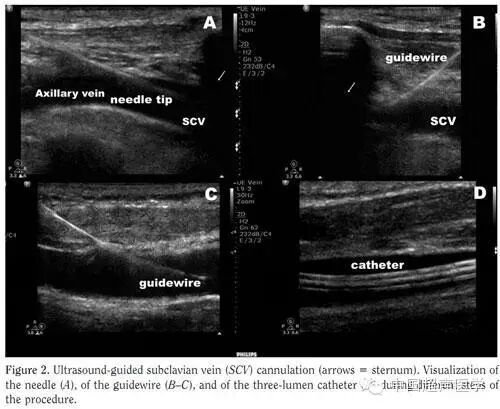

实时超声引导置管法颈内静脉、同侧及对侧的锁骨下静脉区域常规消毒铺巾,采用An HD11 XE超声机(Philips, Andover, MA)以及7.5-MHz高分辨率探头。超声引导置管分为以下四步:1)探查明确腋静脉,锁骨上下静脉的深度和直径以及周围的解剖结构 2)继续纵向探查锁骨下以确定最佳置管平面 3)超声引导下穿刺锁骨下静脉 4seldinger技术置入导管,超声确定导管位置,若穿刺失败行对侧穿刺。